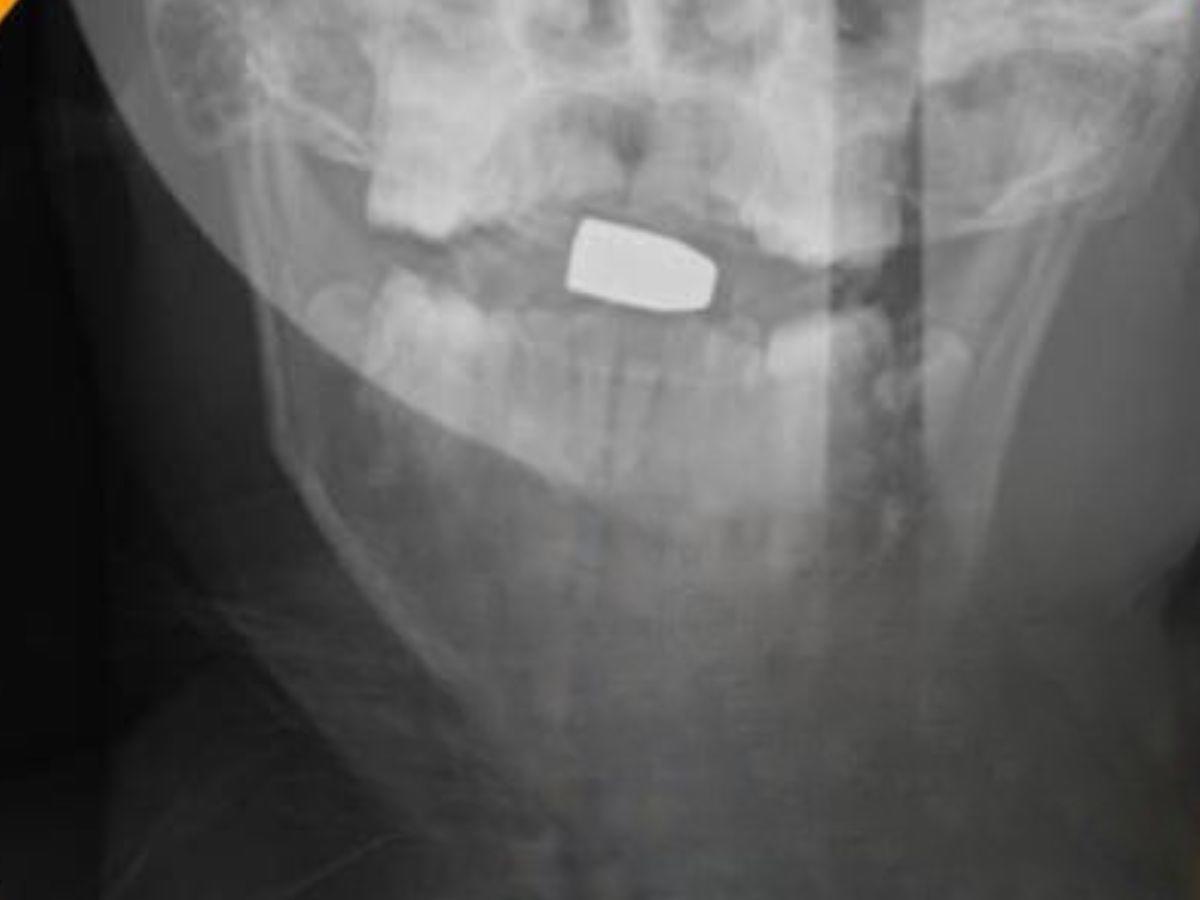

Lamentablemente, Emerson no logró sobrevivir. Radiografías muestran que la bala impactó entre la médula espinal y el cerebro, acabando así con su vida.